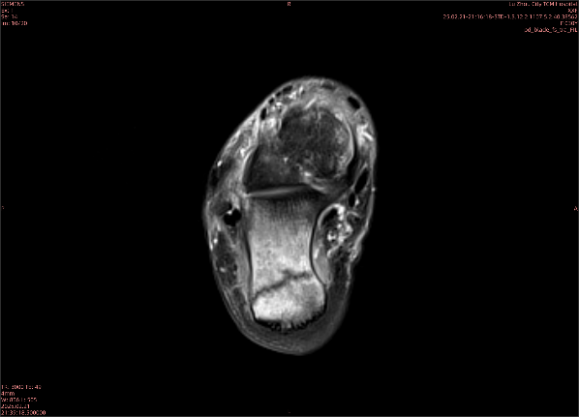

舉例圖像

圖1

專業(yè)解釋看不懂沒關(guān)系,大家看圖1和圖2就可以了,這是同一個(gè)患者跟骨的磁共振和CT圖像,圖1的紅色箭頭指示的黑線就是磁共振圖像顯示的骨折線,一目了然。而對(duì)比圖2的CT圖像上并未顯示異常。

這下大家明白了吧,如果懷疑隱匿性骨折優(yōu)先選擇磁共振檢查